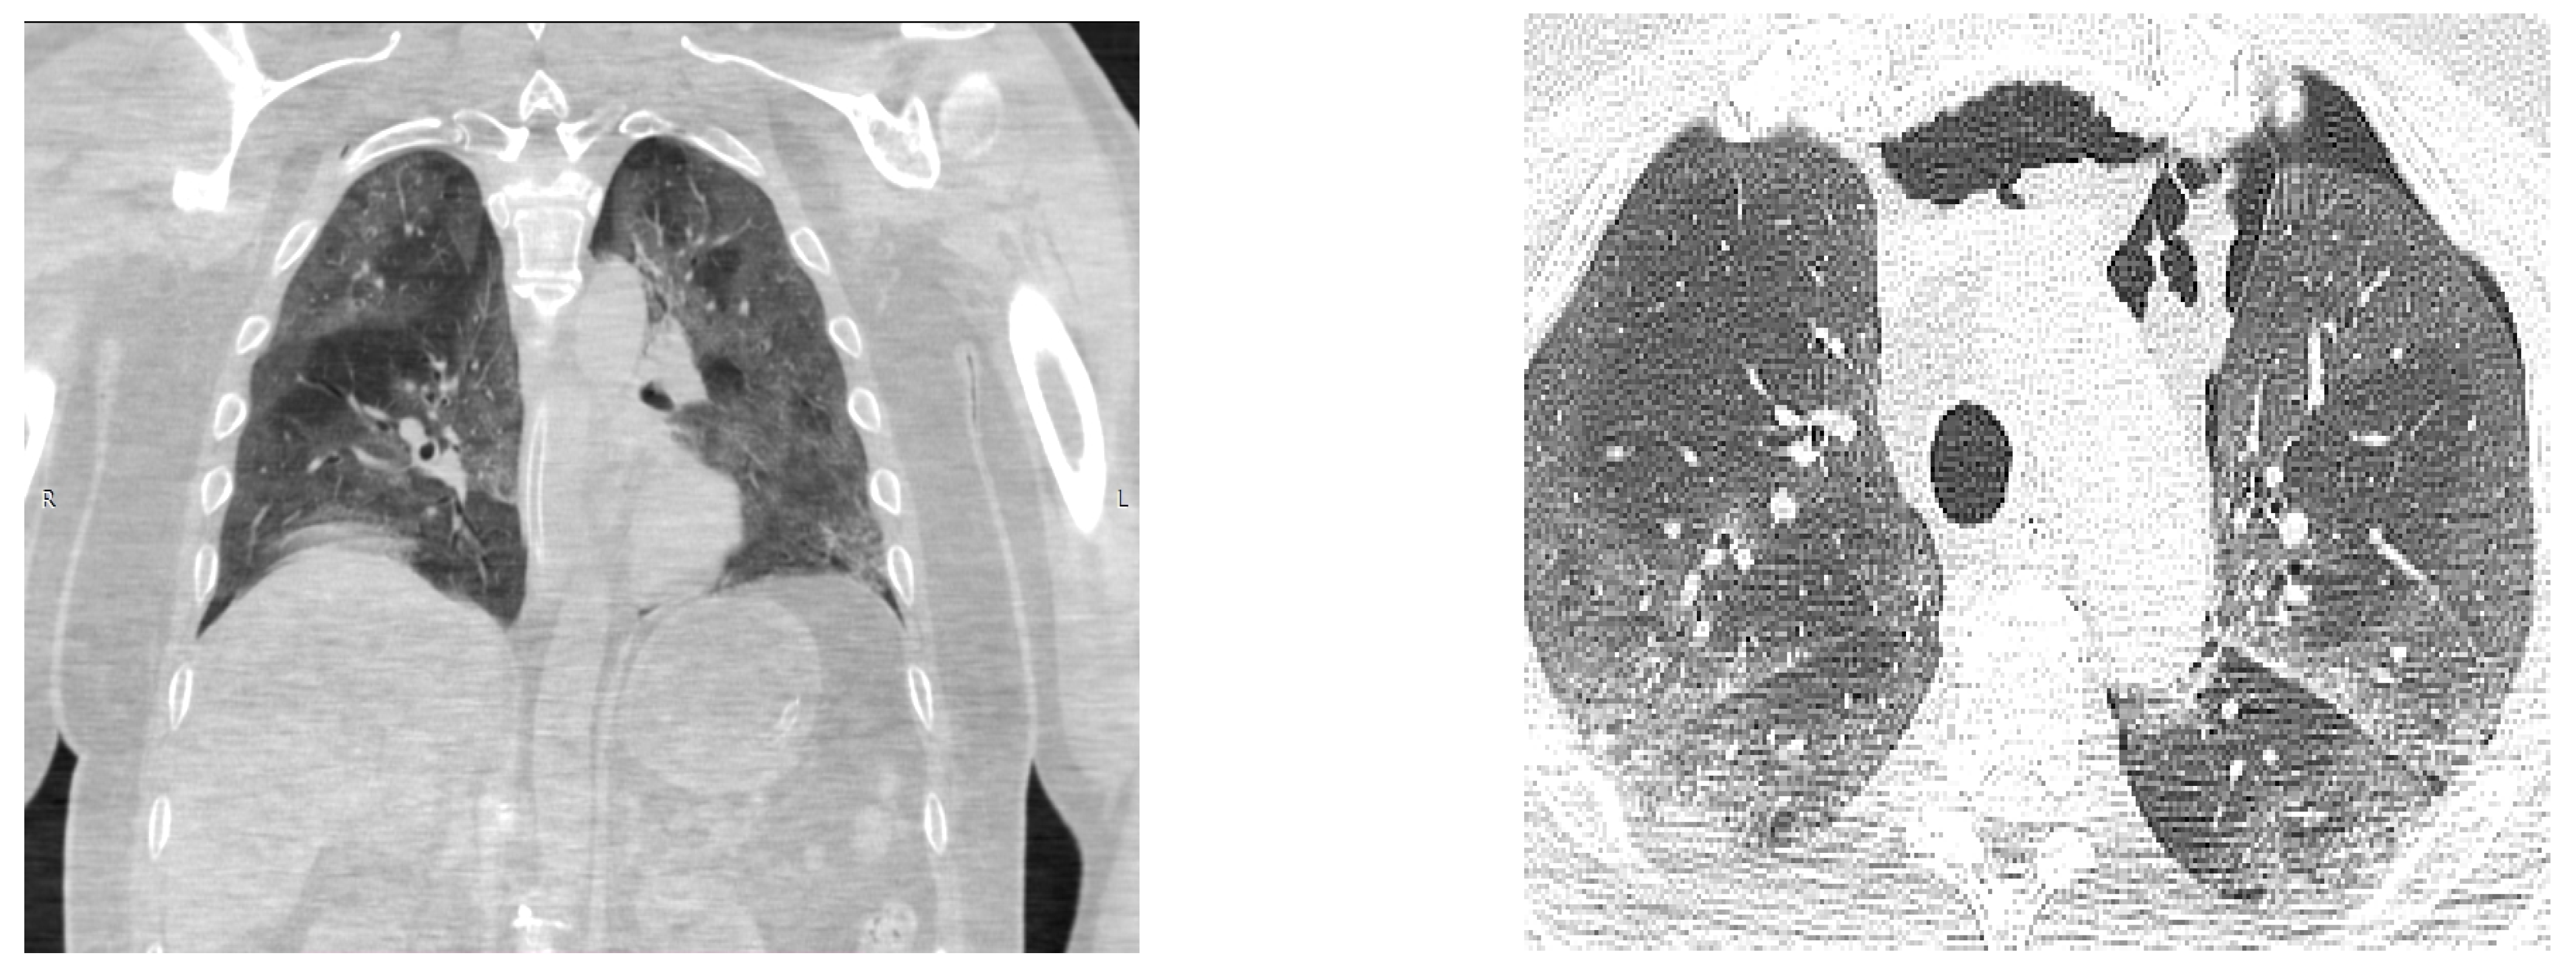

On the 13th day of admission, head and chest CT scans were performed, Figure 1 and Figure 2, from which a diagnosis of a massive ischemic stroke in the territory of the left median carotid artery and the bilateral anterior cerebral artery was made, and it converted to a hemorrhagic stroke and pneumomediastinum without surgical indications; they also revealed critical pulmonary impairment due to COVID-19 infection (over 85% of the entire pulmonary parenchyma was affected).

Figure 2. Chest CT scan: Pneumomediastinum, a critical pulmonary impairment due to COVID-19 infection.